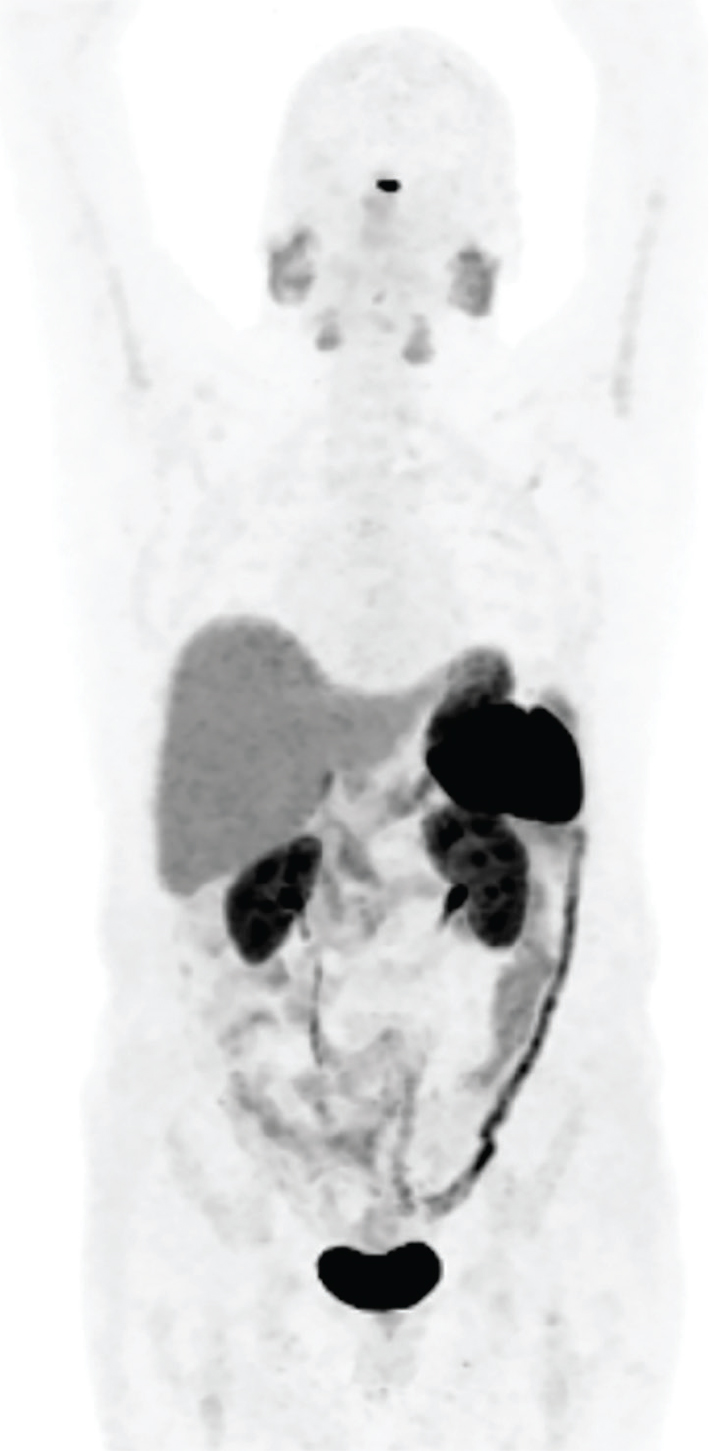

Patients are evaluated by a multidisciplinary NET team, including a medical oncologist, an oncological surgeon, and a nuclear medicine physician (who must be an authorized user) to decide on the appropriateness and timing of PRRT in individual patients. Ideal candidates for PRRT include patients with well-differentiated and moderately-differentiated neuroendocrine carcinomas defined as NET grade 1 or 2 according to the recent WHO 2010 classification (39). Patients considered for PRRT should undergo diagnostic somatostatin receptor imaging such as SSTR PET scan or SSTR scintigraphy (111In-pentetreotide) to demonstrate adequate SSTR expression (40) (Figure 4). The two FDA approved SSTR positron emission tomography (PET) imaging agents are Gallium-68 (68Ga) DOTATATE and Copper-64 (64Cu) DOTATATE. These diagnostic imaging agents constitute diagnostic components of PRRT Theranostics.

Fig 4

Figure 4. A 74-year-old female with advanced and inoperable metastatic ileal NET. A. 68Ga-DOTATATE (SSTR PET) MIP image and B. Fused coronal image show multiple intensely somatostatin receptor-rich tumors in the liver and portocaval lymph node.